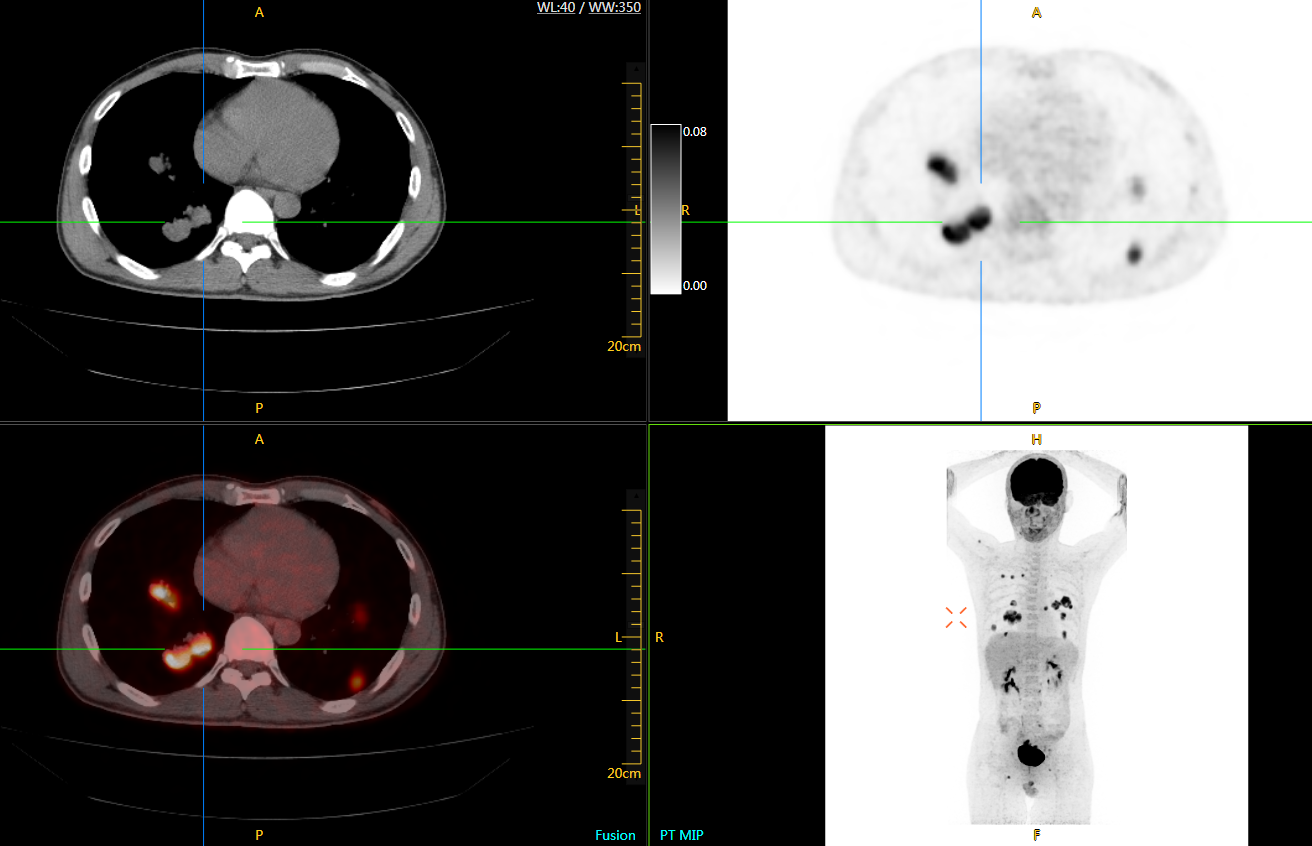

直腸癌

男,45歲,直腸癌術后9個月,發(fā)現(xiàn)肺占位

臨床診斷:直腸區(qū)術后改變,復發(fā)伴骶骨受累,雙肺多發(fā)轉移